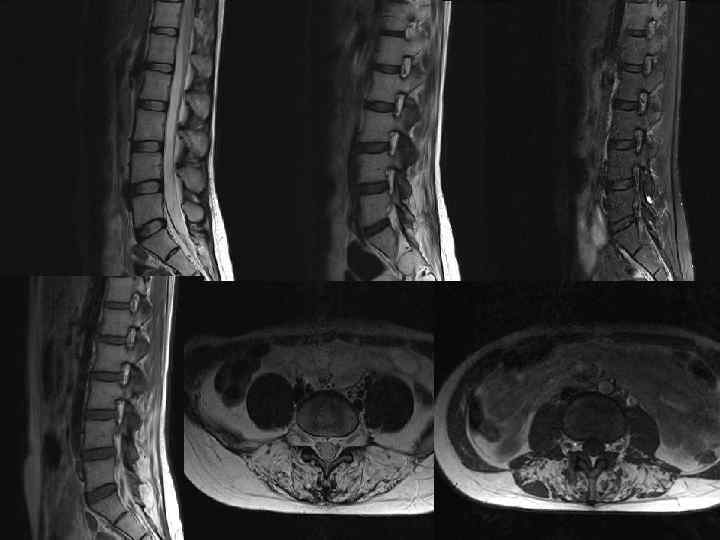

Мрт картина дегенеративно дистрофических изменений пояснично крестцового отдела позвоночника